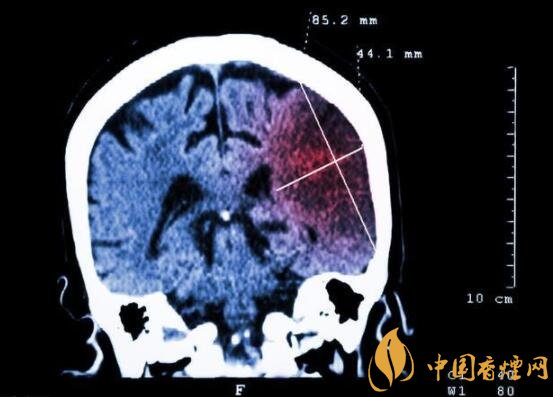

一般而言,急性腦梗塞與長期吸煙有非常密切的聯(lián)系。有長期煙齡遇到肢體活動不順,做頭顱核磁共振檢查往往查出一側(cè)大腦中動脈閉塞的可能性很高。由此可見,吸煙確實與中風(fēng)存在一定聯(lián)系。